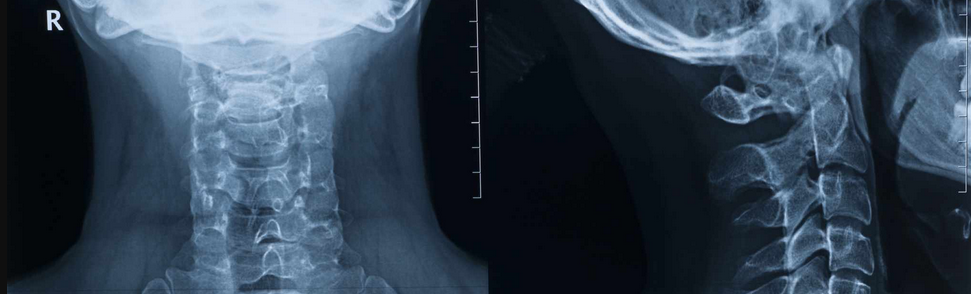

He ran all these tests on me, and looked at my medical history. He pointed out that when I was 18, I was a goalie in a recreational hockey league. I took a slapshot to my face that defied physics and engineering, collapsed my helmet into my forehead, where it split open like an orange peel that was squeezed too tightly. It also gave me whiplash, and herniated two discs in my neck.

But it turns out that, according to the X-ray and other tests he did, I have no soft tissue injury or any tears in any part of my body. The badminton and associated activities just pushed my body past its ability to barely hold itself together.What I do have is no curve in my neck, three almost entirely compressed discs, and a bunch of muscles all doing their best to compensate. These things work together to form Voltron, where Blazing Sword is my arm feeling like it’s experiencing an electrical fire that also itches. Really great stuff. I’ll form the head.